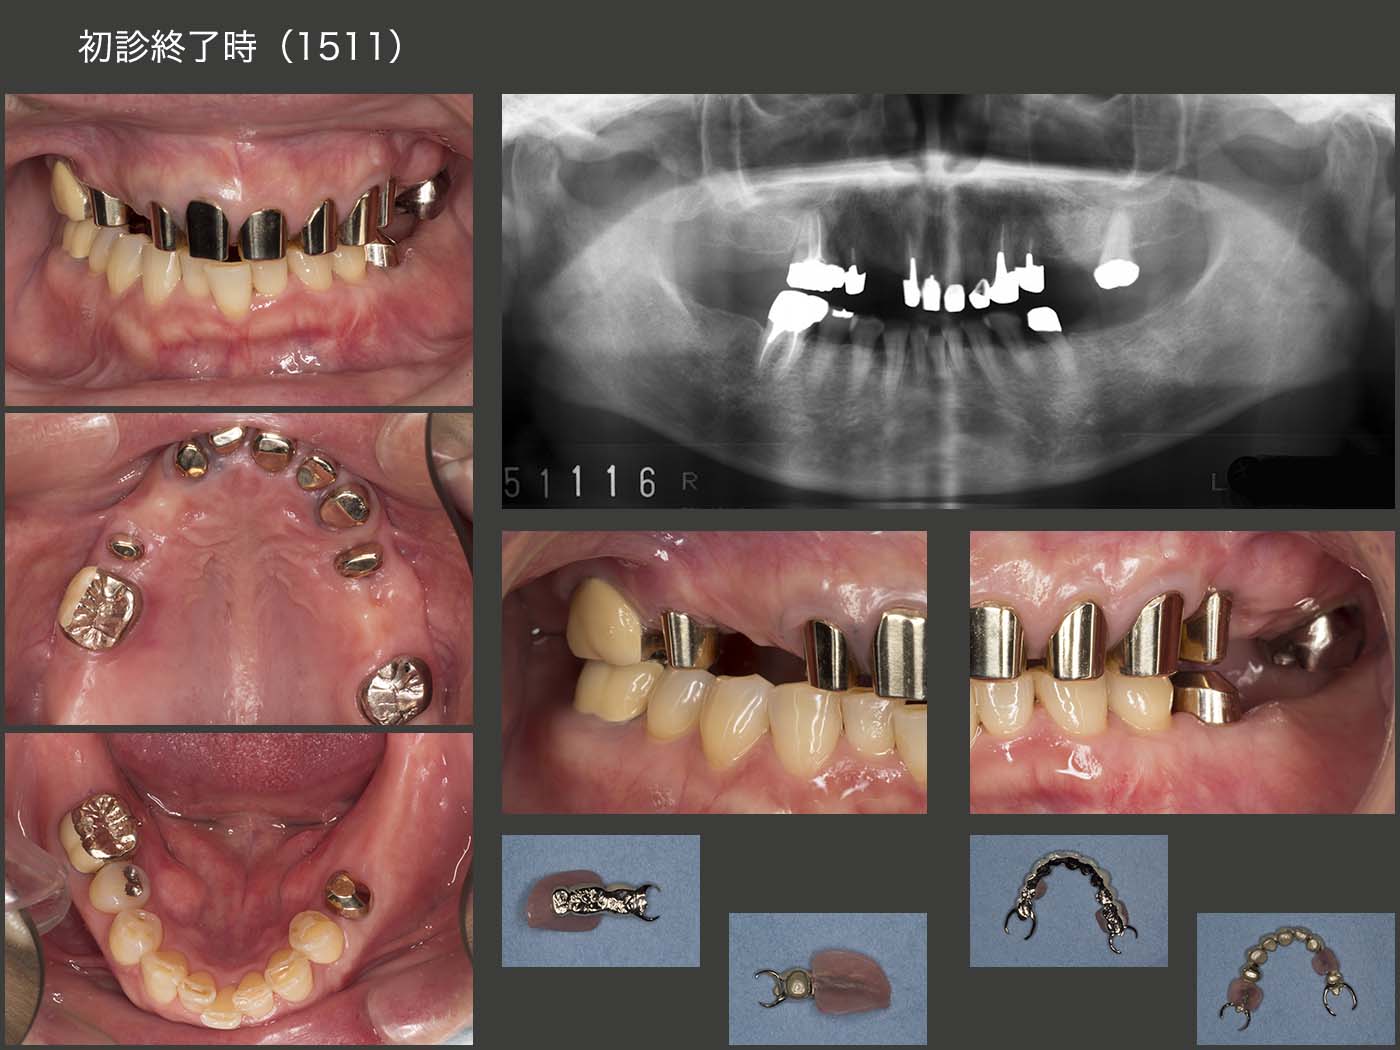

2015年11月,初診終了時の状態.新義歯製作中,咀嚼の中心は右側の上下6であり,これまで,右上6は移植後の歯周ポケットが最大5mmで安定していたが,初診終了時には近心部が7mmまで深化してしまった.

右上6(移植歯)の経過.まずスライド左上は,2013年5月,クラウン装着時の状態であるが,特に問題はない.しかし,15年11月,初診終了時においては,近心に歯周ポケットが7mmあり,デンタルX線写真から近心に透過像が認められる.16年9月の時点では,歯周ポケットが近心で10mmとなったため,クラウンを除去し,力の解放を行った.17年1月に,歯周外科を行い,今度はコーヌス冠を装着して,2次固定効果を期待した.(17年9月装着,歯周ポケットは5mmに回復した.)しかし,18年2月,右上4のコアごと脱離の際,移植歯を精査したところ,頰側歯肉縁下に炎症性吸収が生じ,歯質がなくなっていた.そこをさらに深く追っていくと,上顎洞の穿孔も認められたため,抜去せざるを得なかった.もちろん私の手技が稚拙であることは間違いないが,ここが偏咀嚼主機能歯になったことが大きな要因になったことも否定できない.18年3月,右上4に根面板を装着した.